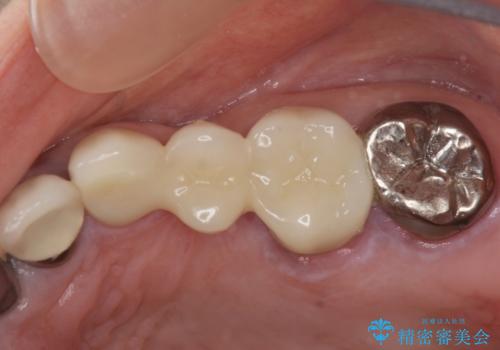

銀歯の見た目を改善、ジルコニア製セラミックブリッジ

- 39.6万円(ジルコニアクラウン×3・仮歯×3)費用は治療当時の料金となります

ジルコニア製セラミックブリッジは、審美性にすぐれた補綴方法です。